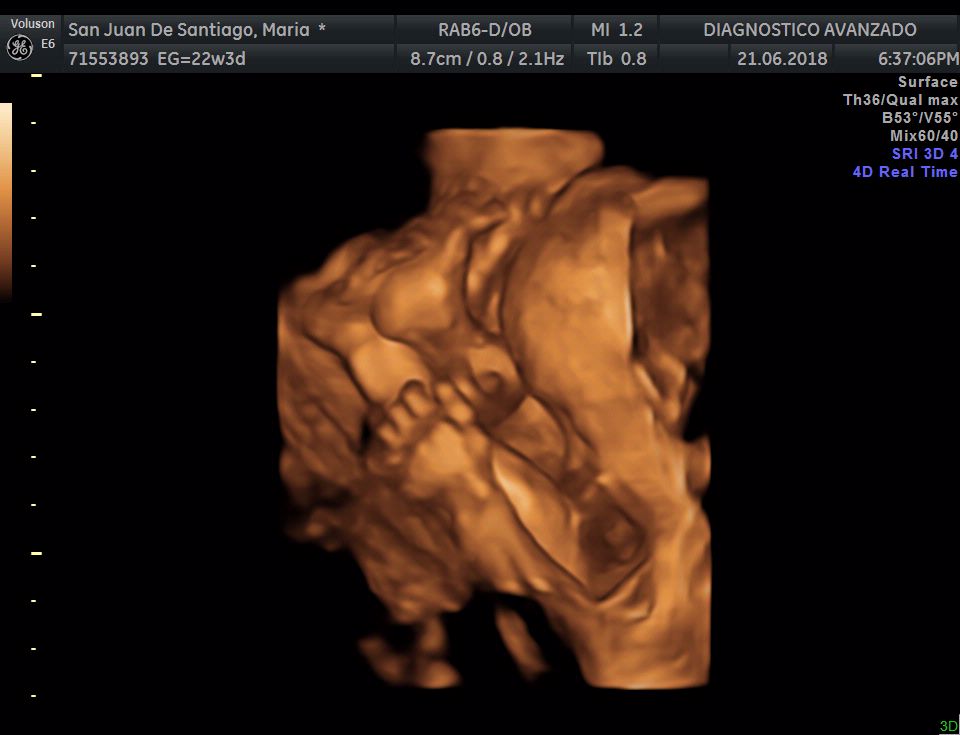

¡Hola a todos! Hoy hemos ido a hacer la tradicional ecografía 3D de la niña, os dejamos todo el material (aunque es un poco demasiado).